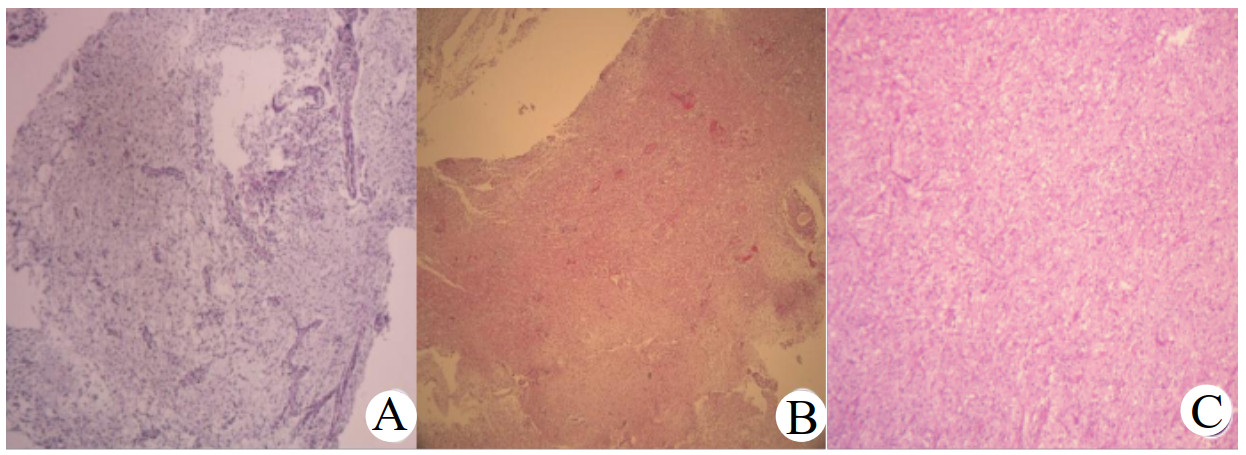

2.3 治疗方案及预后随访5例患儿确诊后均行鞍区肿块次全切术,术后病理结果均为低级别胶质瘤,病例1、2、4为毛细胞星形细胞瘤;病例3为毛细胞黏液样星形细胞瘤,病例5为节细胞胶质瘤。见图 1。

| 注:A为病例3,毛细胞黏液样星形细胞瘤;B为病例4,毛细胞星形细胞瘤;C为病例5,节细胞胶质瘤: 镜下见胶质细胞增生,弥漫分布,可见散在神经节细胞 图 1 3例DS患儿病理学结果 |